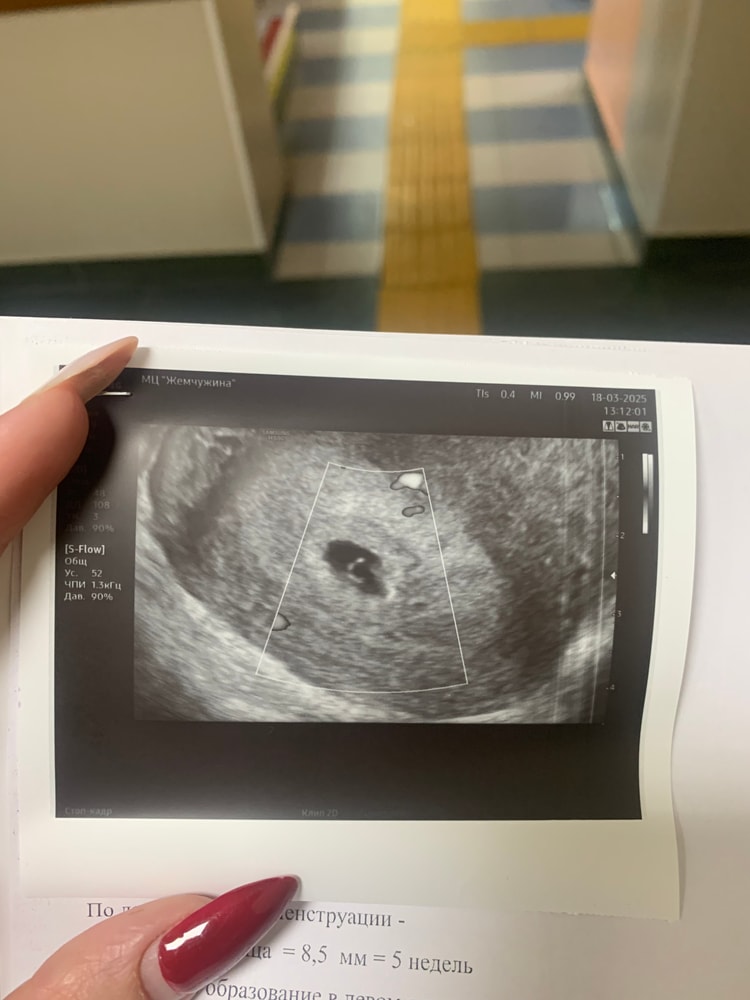

Я делала рано узи. У меня в день типа месячных вечером на бумаге после похода в туалет была светло-коричневая мазня. На след день я поехала в больницу, потому что распереживалась. Узи сделала трансвагинально, был срок тогда 4+1 недели, увидели только жт и что-то крохотное еще. Выделений больше не было, хгч в динамике показал рост. Через 3 дня я узи повторила тоже трансвагинально, увидели маленькое плодное яйцо. Тогда хгч был 2100.